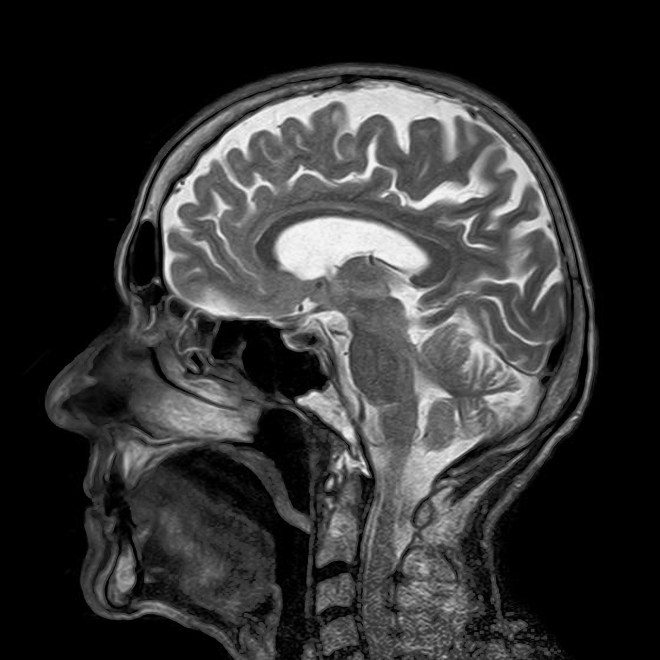

When I look at an MRI scan, I also see patterns:

and my brain does something similar… In essence, my brain is simplifying the structure, highlighting some differences and reducing others. It’s filtering the image down to something like this:

BUT the gradations of grey-scale on a sofa don’t mean the same thing as in an MRI scan of the brain. The original image actually contains far more gradations of grey than I can probably perceive…

The “ghosts” in this process are a level of visual processing that our brains often carry out below the surface, recognizing some shades of grey as the “same” and clustering them, ignoring others and filtering them out. There’s simply no guarantee that the way this is happening – trained by all kinds of situations in which we recognize patterns in images – will pick up the critical differences in an MRI image of the brain.